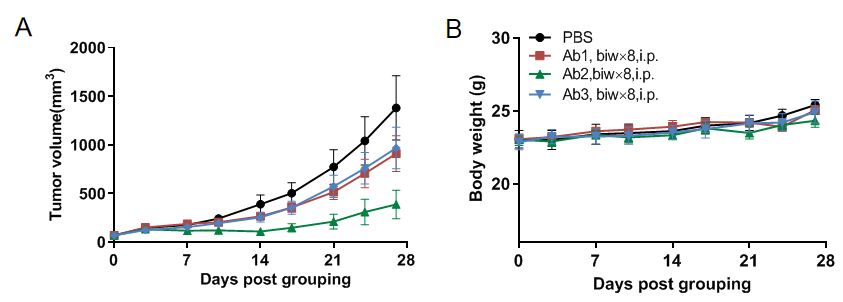

Antitumor activity of anti-human CD16A-based Ab in B-hCD16A mice.

(A) Anti-human CD16A-based Ab inhibited MC38 tumor growth in B-hCD16A mice. Murine colon cancer MC38 cells were subcutaneously implanted into homozygous B-hCD16A mice (female,13-week-old, n=7). Mice were grouped when tumor volume reached approximately 70 mm3, at which time they were treated with anti-human CD16A-based Ab with doses and schedules indicated in panel B. (B) Body weight changes during treatment. As shown in panel A, anti-human CD16A-based Ab was efficacious in controlling tumor growth in B-hCD16A mice, demonstrating that the B-hCD16A mice provide a powerful preclinical model for in vivo evaluation of anti-human CD16A-based Ab. Values are expressed as mean ± SEM.